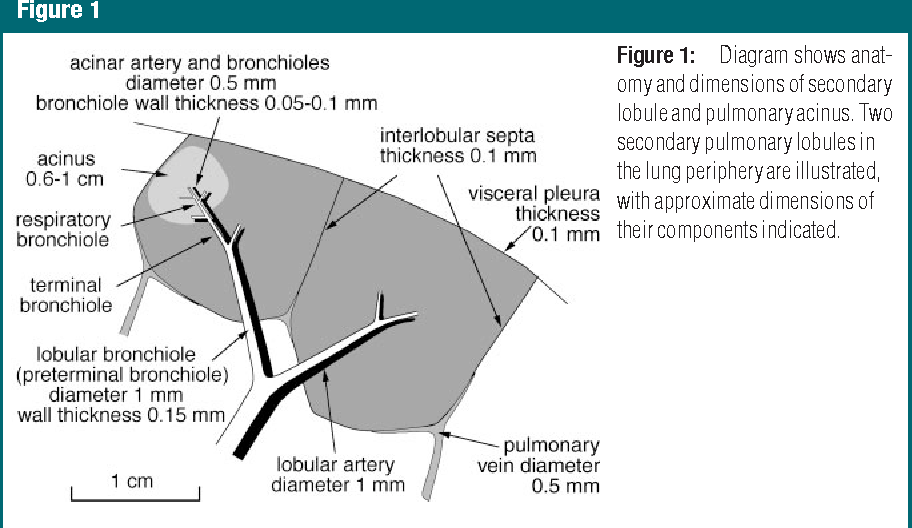

Secondary Pulmonary lobule

The secondary pulmonary lobule is the elemental unit of lung function. Each SPL contains a central artery (the aptly named centrilobular artery) and a central bronchus, each branching many times to ultimately produce acinar arteries and respiratory bronchioles. On CT, the centrilobular artery is often visible as a faint dot. The centrilobular bronchus is not normally visible. The acinus is the basic unit of gas exchange, containing several generations of branching respiratory bronchioles, alveolar ducts, and alveoli. There are generally 12 or fewer acini per secondary lobule. Pulmonary veins and lymphatics collect in the periphery of each SPL. Connective tissue, called interlobular septa, ecases each SPL. Thickening of the interlobular septa can be seen on CT and suggests pathologic enlargement of either the venous or lymphatic spaces. Each SPL is between 1 and 2.5 cm in diameter.